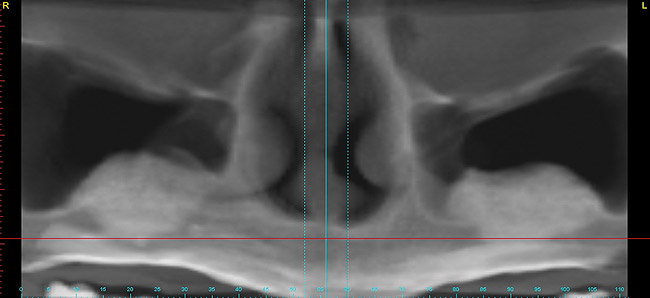

Figure 14  Panographic view showing large facial bone defects.

Figure 14

Figure 15  Axial view showing large facial defects.

Figure 15

A 53-year-old woman in good health presented for the replacement of missing teeth on the maxillary arch and periodontal therapy of the mandibular arch. A CBCT scan was taken that revealed the need for bone grafting on the maxillary ridge and maxillary sinus areas in the panographic (Figure 14) and axial (Figure 15) views. Bone loss was noted on the facial plate areas of the anterior ridge. A treatment plan was created to graft the maxillary ridge and sinuses bilaterally, and then to place 12 dental implants to support a fixed prosthesis on the maxillary arch.The treatment plan for the mandible consisted of periodontal surgery to save her remaining teeth.